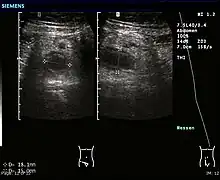

Ultrasound image of acute appendicitis

Abdominal ultrasonography, preferably with doppler sonography, is useful to detect appendicitis, especially in children. Ultrasound can show the free fluid collection in the right iliac fossa, along with a visible appendix with increased blood flow when using color Doppler, and noncompressibility of the appendix, as it is essentially walled-off abscess. Other secondary sonographic signs of acute appendicitis include the presence of echogenic mesenteric fat surrounding the appendix and the acoustic shadowing of an appendicolith.[55] In some cases (approximately 5%),[56] ultrasonography of the iliac fossa does not reveal any abnormalities despite the presence of appendicitis. This false-negative finding is especially true of early appendicitis before the appendix has become significantly distended. Also, false-negative findings are more common in adults where larger amounts of fat and bowel gas make visualizing the appendix technically difficult. Despite these limitations, sonographic imaging with experienced hands can often distinguish between appendicitis and other diseases with similar symptoms. Some of these conditions include inflammation of lymph nodes near the appendix or pain originating from other pelvic organs such as the ovaries or Fallopian tubes. Ultrasounds may be either done by the radiology department or by the emergency physician.[57]